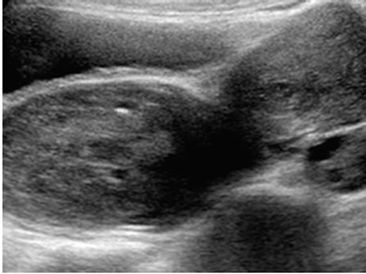

La ecografía pélvica demostró tumor heterogéneo de 6 centímetros de diámetro que protruía hacia el abdomen con útero y ambos anexos de tamaño normal (figura 1). No se apreciaron signos de ascitis o adenopatías pélvicas. La evaluación doppler color mostró una vascularización interna significativa con flujo arterial y venoso con vascularización de útero y ambos anexos dentro de límites normales.

El rabdomiosarcoma urogenital tiene una presentación clínica que varía según la localización del tumor. Sangrado, tumoración palpable, leucorrea y alteraciones urinarias o evacuatorias son los síntomas más comunes. El hallazgo más frecuente en el rabdomiosarcoma vaginal es el sangrado, mientras que los tumores vesicales pueden manifestarse principalmente con síntomas urinarios (9). La radiología convencional no es útil para el diagnóstico del rabdomiosarcoma. La ecografía se considera el primer método de evaluación porque permite visualizar masas heterogéneas, bien definidas y con flujo sanguíneo elevado (11). La resonancia magnética, por otro lado, ofrece una caracterización más detallada del tejido, generalmente mostrando una intensidad de señal intermedia en secuencias T1 y alta en secuencias T2, y con frecuencia presenta un aspecto quístico multiseptado debido al estroma mixoide (12,13).